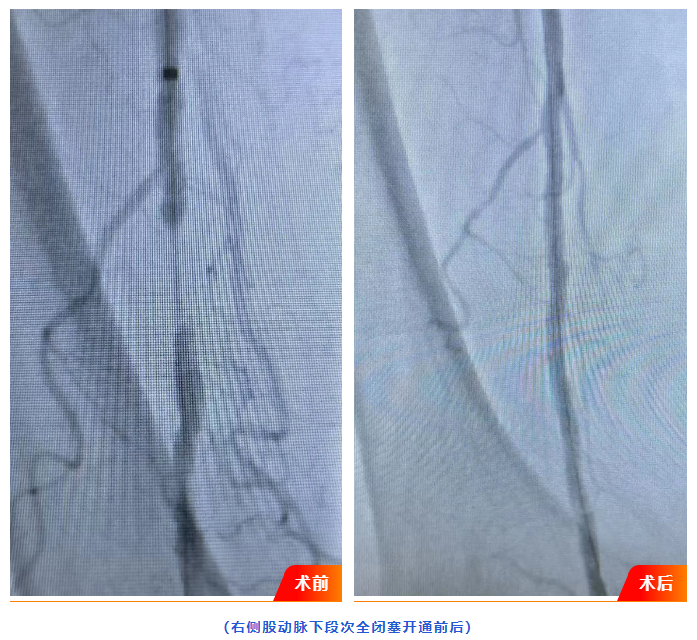

浏览量:1543月18日,广水一医院介入血管科成功为82岁高龄患者实施县域首例下肢动脉闭塞介入开通手术。此项手术的成功开展,填补了广水县域内血管介入治疗的技术空白,为周边地区下肢动脉疾病患者带来更高效、精准的诊疗选择。

患者刘某,82岁,3月13日因右下肢疼痛肿胀3月余入院,经下肢动脉CTA影像检查见其下肢动脉粥样硬化闭塞严重,同时合并右足趾骨皮肤湿性坏疽及谵妄症状,病情复杂危重。若不及时干预,患者将面临截肢甚至生命危险。

面对高龄、多系统并发症等挑战,广水一医院迅速启动多学科联合诊疗(MDT)机制,介入血管科联合内分泌科、骨科、神经内科等专家进行会诊,结合患者身体状况及影像学结果,最终确定为患者施行创伤小、恢复快的“下肢动脉闭塞介入开通”微创手术方案。

18日,介入血管科负责人刘自力及科室团队经右侧股动脉穿刺置入导管,利用球囊扩张成功开通患者闭塞的下肢动脉。术后患者右下肢疼痛、肿胀症状显著缓解。经观察,患者生命体征平稳,恢复良好,目前已顺利出院。